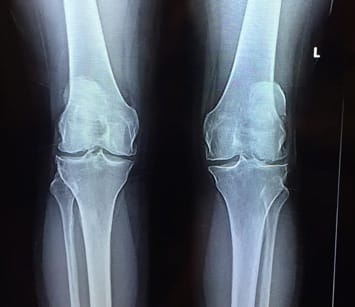

July 2016

April 2017

Female, 54 years old

Debilitating Bilateral Knee Pain

Numerous knee dislocations to both knees – (over 20 times)

Recommended arthroscopic surgery at age 22. She was told she would need a knee replacement in her 40’ or 50’s.

She did rehab, nutrition (glucosamine and chondroitin sulfate), chiropractic, and HA injections.

For the past 30 years, she could not sit crisscross, wear high heels for more than a couple hours, or run at all. She had difficulty going up and down stairs, and could not do a full squat.